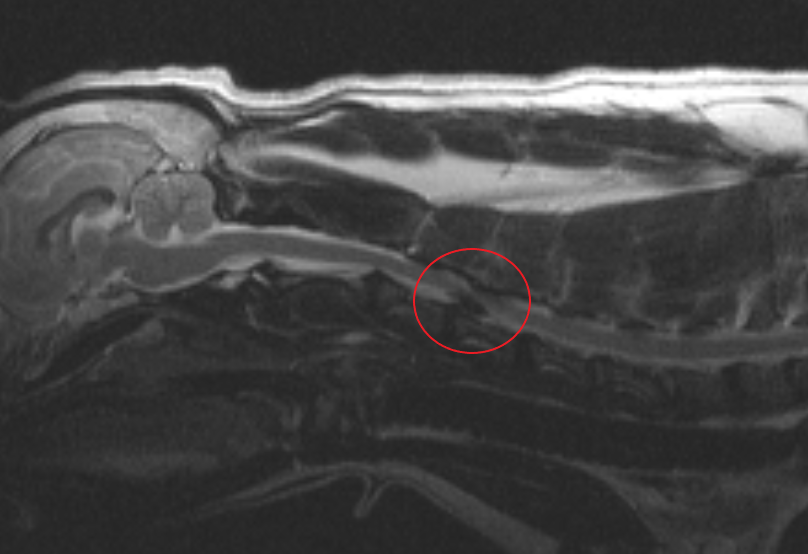

При межпозвоночных грыжах в шейном отделе позвоночника (рисунок 2), мы проводим операцию под названием «вентральный слот» или «вентральный пропил», в этом случае оперативный доступ осуществляется через тела шейных позвонков с вентральной поверхности шеи.

Рисунок 2 – Экструзия межпозвоночного диска у собаки в шейном отделе